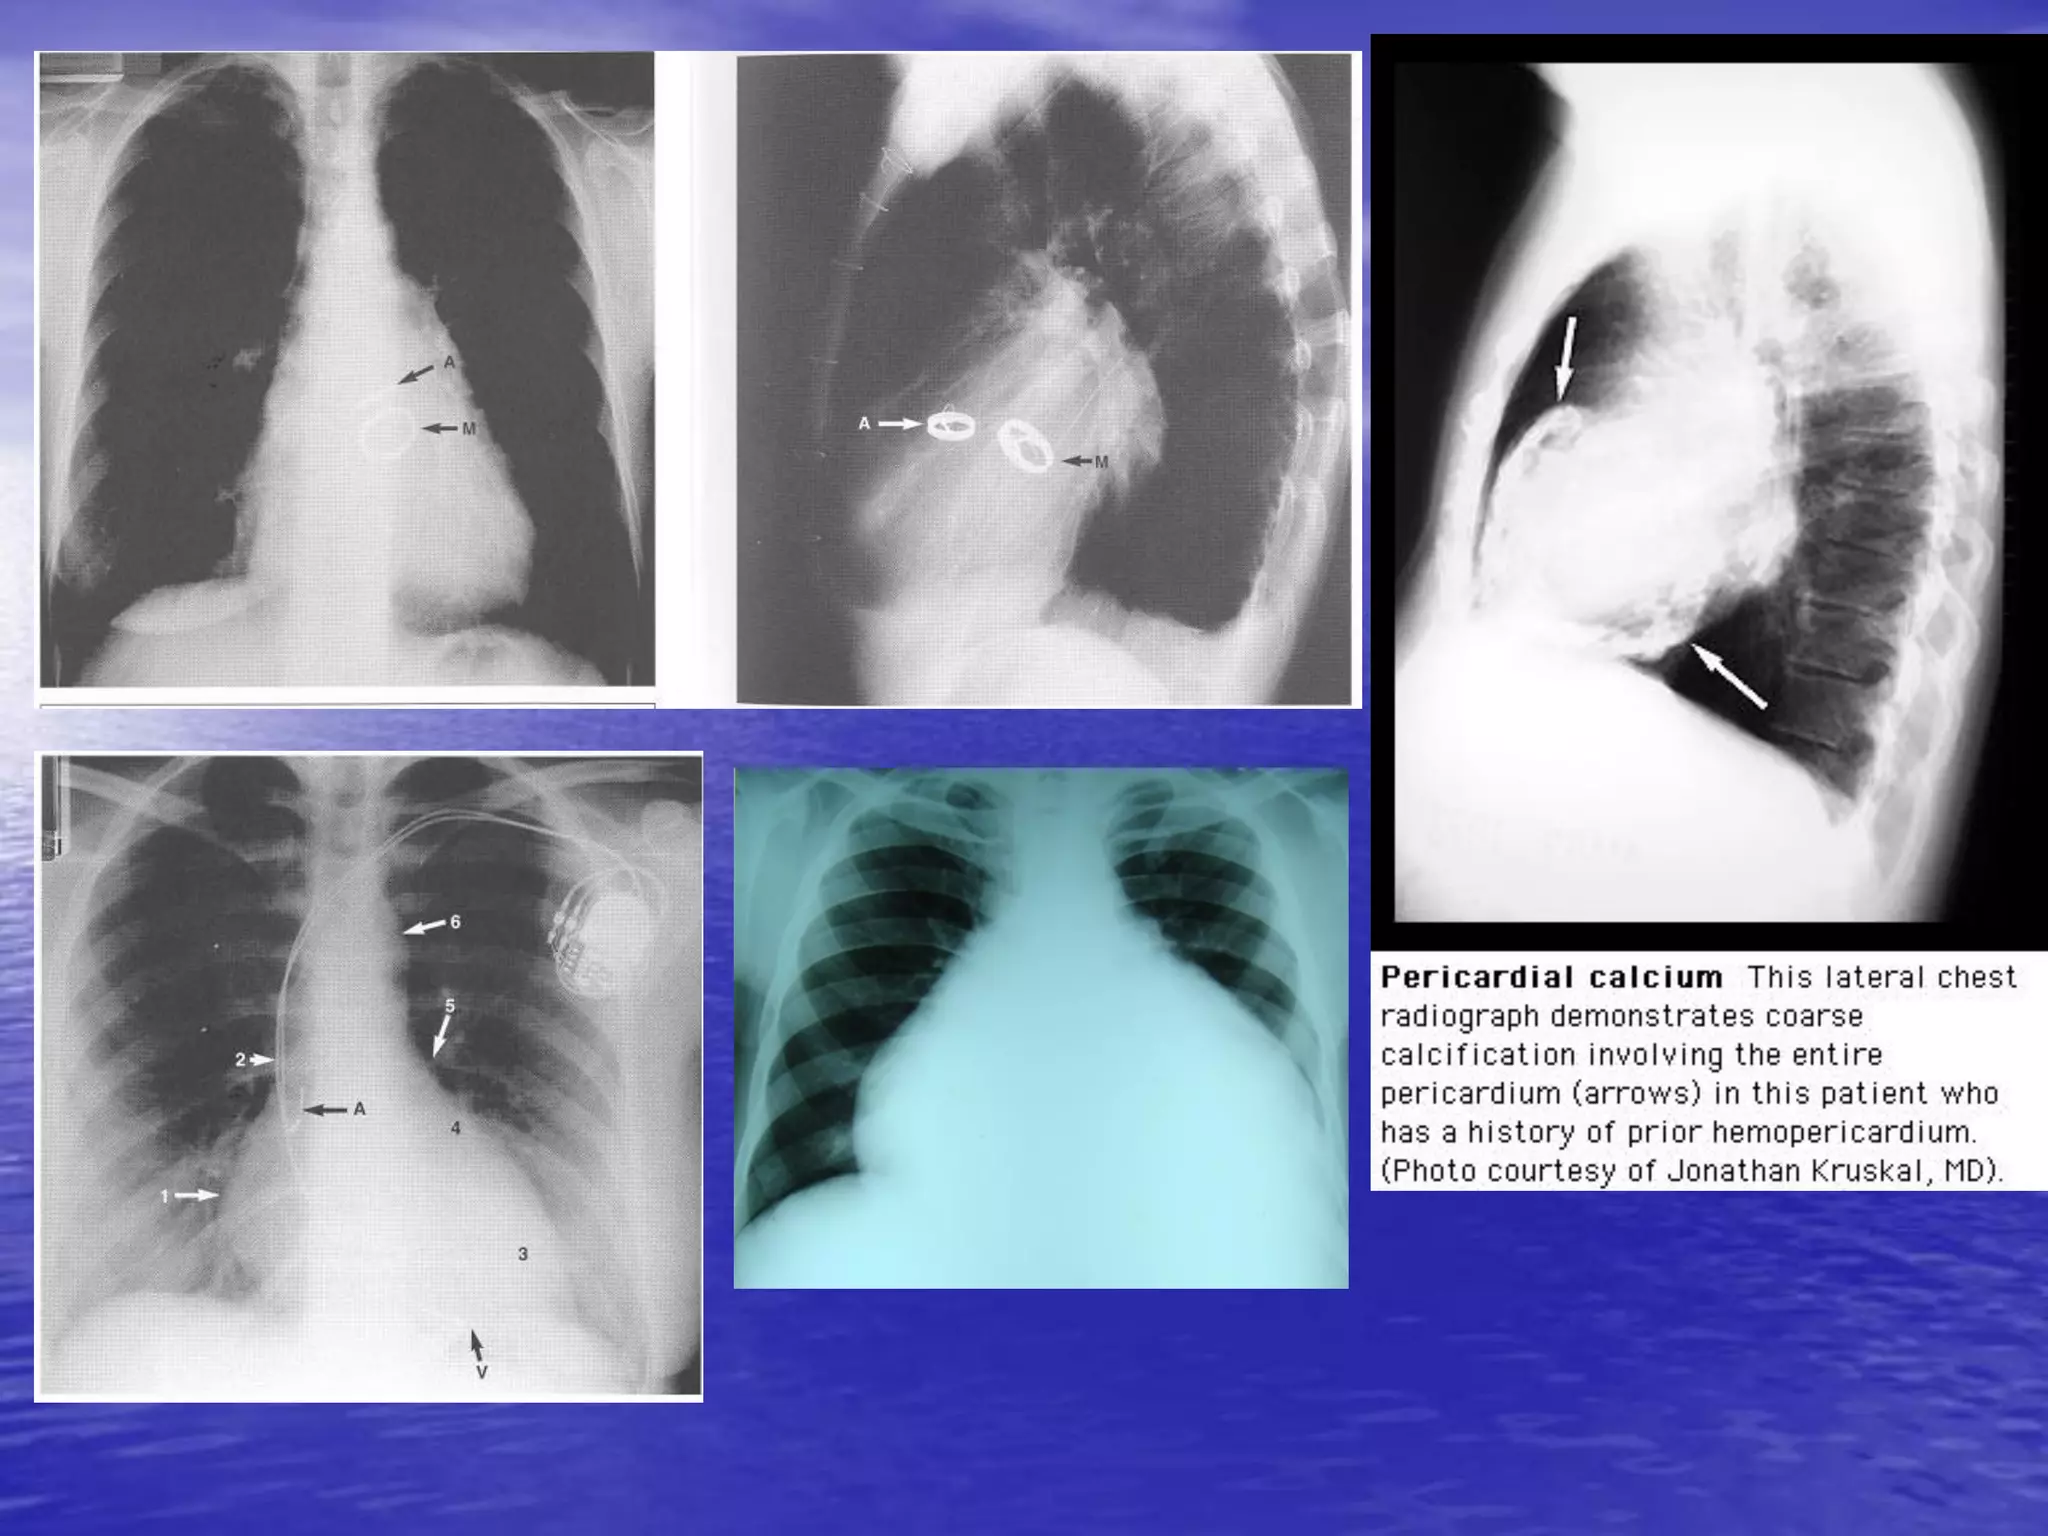

1 số hình ảnh khác

1 số hìnhảnh khác